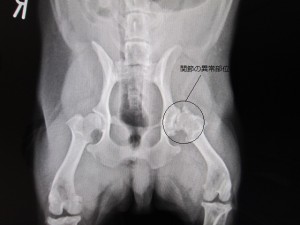

術後

術後のレントゲンです。

左大腿骨頭を切除しました。